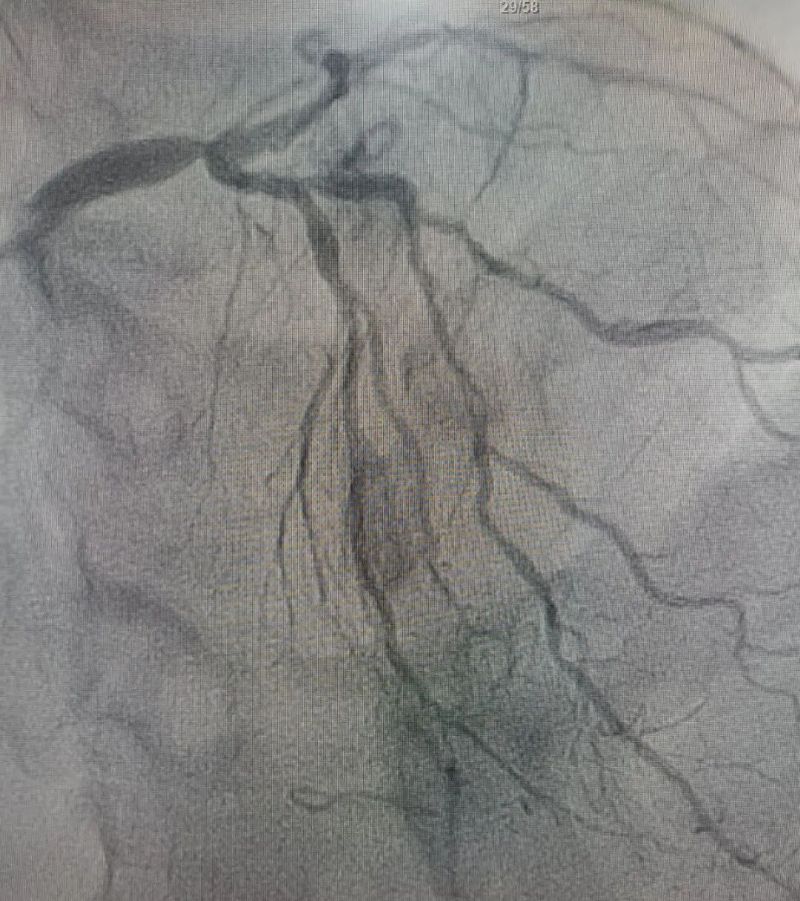

術中造影顯示,左主干至前降支近段重度狹窄——這正是導致心臟缺血、誘發室顫的“罪魁禍首”。主動脈球囊反搏植入、球囊擴張、支架植入......介入團隊精準操作,一氣呵成。堵塞的血管順利開通,血流重新涌動,這顆一度瀕臨停跳的心臟終于重獲生機。

冠狀動脈造影圖

術前 (左主干至前降支近段重度狹窄)

術后(左主干至前降支近段原狹窄消失)